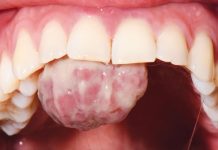

Trattamento chirurgico di un granuloma piogenico in gravidanza

Con il termine granuloma piogenico (GP) si intende una proliferazione tissutale in eccesso provocata da uno stimolo irritativo noto (1). Il principale fattore eziologico...